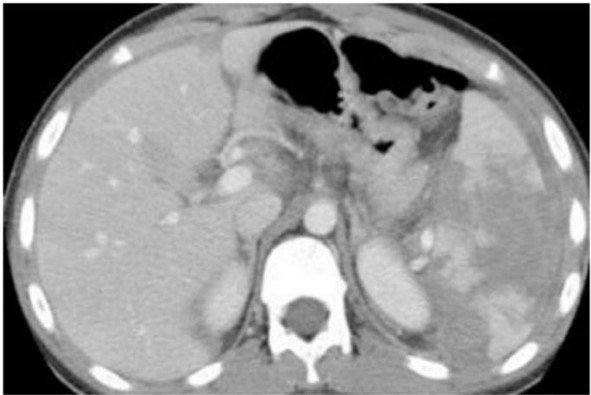

Homem de 25 anos foi vítima de colisão de carro contra muro, sendo atendido inicialmente pela equipe pré-hospitalar com médico (Suporte Avançado). Chega intubado, em ventilação mecânica; pressão arterial: 80 × 60 mmHg; frequência cardíaca: 140 bpm, Glasgow: 6T. Após expansão com 2.000 mL de solução cristaloide: pressão arterial 100 × 70 mmHg, frequência cardíaca: 120 bpm. Indicada então tomografia de abdome, ilustrada a seguir. Após a tomografia, apresentou novamente hipotensão com aumento da taquicardia.

Qual é a opção CORRETA para o tratamento da lesão abdominal deste paciente?